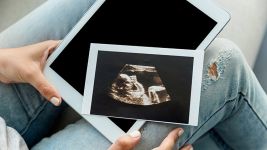

Vanmaterična trudnoća: Rani znakovi i važnost pravovremene dijagnoze

Šta je vanmaterična trudnoća?

Vanmaterična trudnoća je implantacija oplođenog jajeta van materice, najčešće u jajovodu, što je opasno po život i zahteva hitnu...